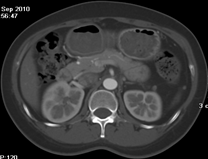

如上圖所示,相鄰的三張軸位圖像未見明顯異常,根據(jù)傳統(tǒng)軸位圖像很難得到準確的臨床診斷。

同一病人利用容積數(shù)據(jù)進行三維處理后,高品質(zhì)MPR和三維圖像上則清晰顯示了縱向排列的腹腔干與腸系膜上動脈相鄰近,血管發(fā)生變 異,近端血管閉塞,為臨床提供了精確的診斷信息。